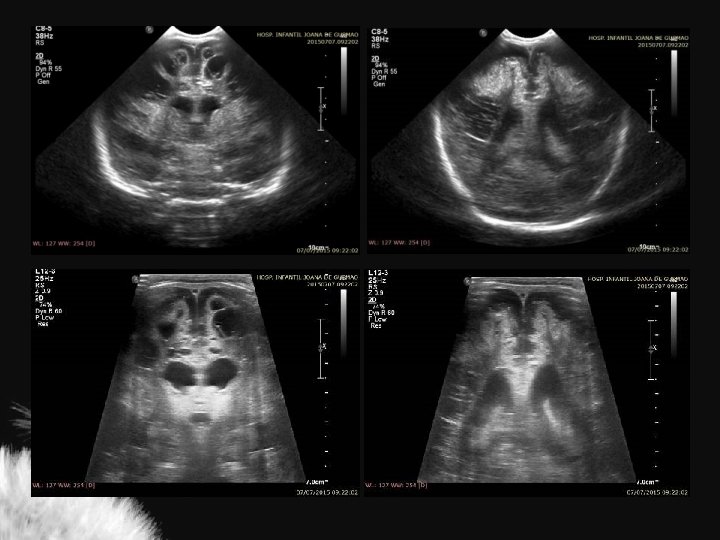

Hidrocefalia benigna da infância – sinal da veia cortical positivo

Coleção subdural – sinal da veia cortical negativo